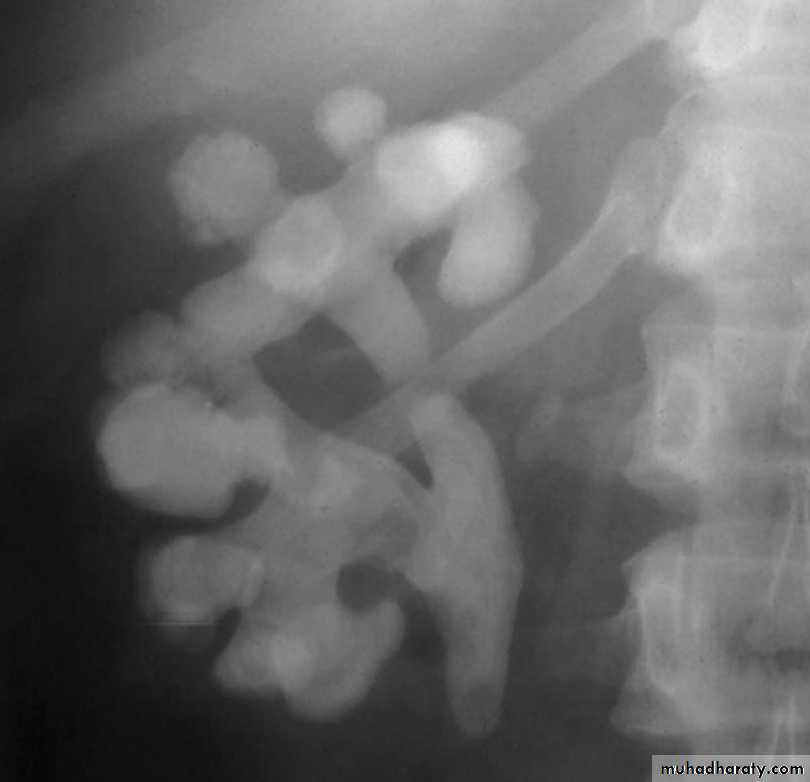

High density renal stonesStage horn calculus KUB filmsradio opaque stones

Failure of contrast to pass to ureters due to both sided mid ureteric stones

LT sided upper Ureteric stones